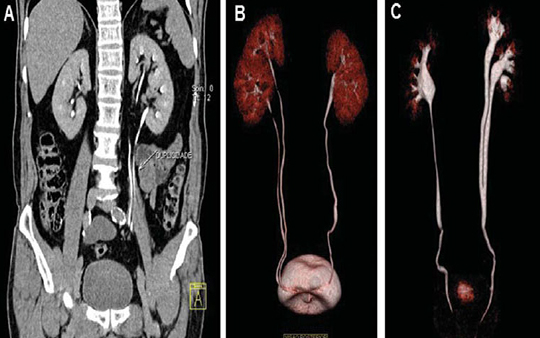

În urma investigaţiilor necesare (analiza generală a sângelui şi a urinei, ultrasonografia sistemului urinar, urografia intravenoasă, scintigrafia dinamică renală), consultaţia medicilor specialişti (după necesitate), se va stabili diagnosticul şi conduita de tratament. După obţinerea rezultatelor examinărilor de laborator şi imagistice, medicul trebuie să discute rezultatul cu dumneavoastră şi să vă comunice posibilitățile de tratament.